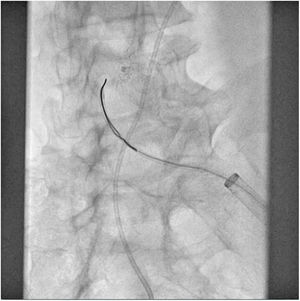

El paciente se traslada a la sala de hemodinamia donde se intenta la extracción del dispositivo. Se utilizan diferentes catéteres lazo de 10, 25 y 30 mm, así como lazos de fabricación con guías largas y cortas intentando movilizar el dispositivo desde diferentes accesos vasculares (acceso bifemoral 6 y 18 Fr y radial 6 Fr) (figuras de la 1 a la 4). Se produce como complicación disección de aorta abdominal con extensión a arteria ilíaca común derecha (figuras 5 y 6) y pérdida total del flujo en extremidad inferior ipsilateral con signos y síntomas de isquemia arterial aguda, por lo que el paciente es trasladado de forma urgente al quirófano de angiología y cirugía vascular. Se realiza disección de aorta abdominal infrarrenal vía laparotomía media con aortotomía longitudinal en el lugar de la localización del cuerpo extraño visualizándose el dispositivo migrado anclado a la íntima-media de la pared arterial. Se procede a su extracción y posteriormente se realiza cierre de aortotomía con parche de pericardio bovino fijando la disección y corrigiendo así el defecto (figuras de la 7 a la 9). El paciente sale de quirófano con pulso pedio bilateral y excelente perfusión distal.